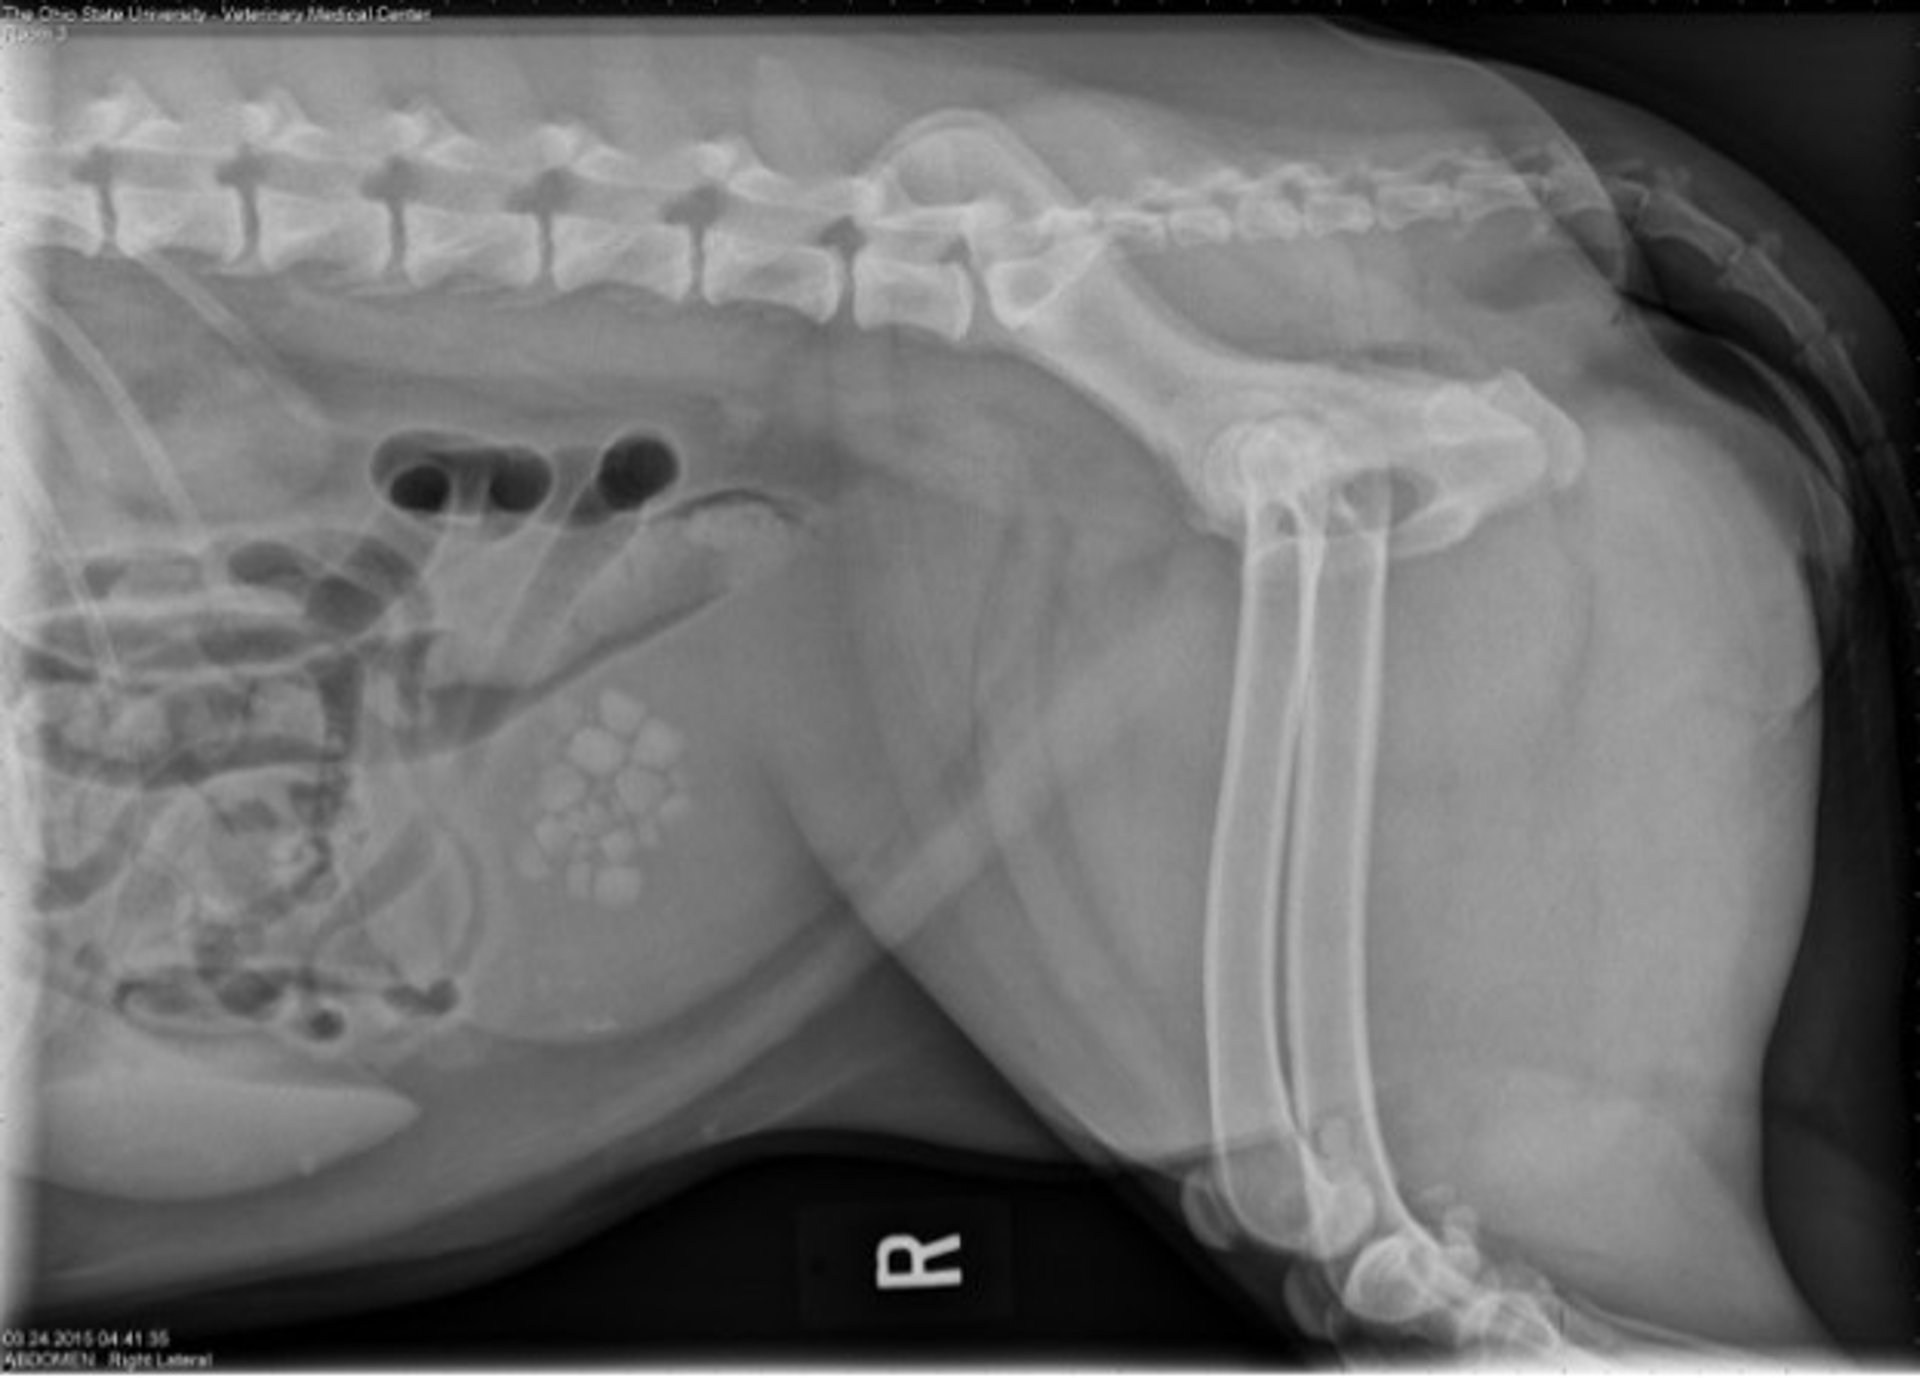

Radiografía lateral de un perro con hiperparatiroidismo primario y cálculos vesicales de oxalato cálcico.